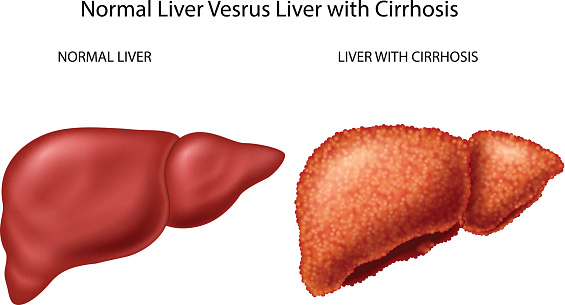

Everything we do and take in somehow affects our liver. Our liver performs over 500 functions that work to keep us healthy overall. But what do we do when the liver gets sick? Your best defense against a sick liver is to adhere to a healthy lifestyle as much as possible. It’s really that simple. ...click here to read more